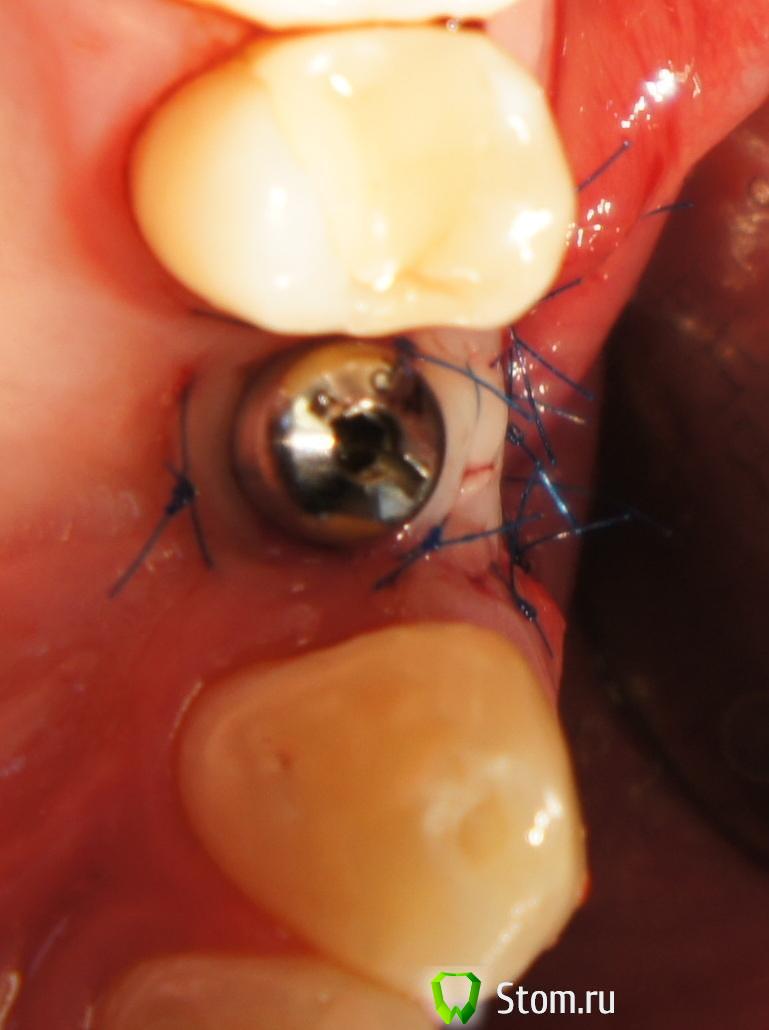

FBR Опубликовано 12 апреля, 2012 Поделиться Опубликовано 12 апреля, 2012 Добрый день коллеги! Провел пластику СДТ в области 24. Буду признателен за комментарии и советы. (извините за качество фотографий, я только начал. В последствии исправлюсь...). Ссылка на комментарий

FBR Опубликовано 12 апреля, 2012 Автор Поделиться Опубликовано 12 апреля, 2012 (изменено) Объем добавить хотелось, и прикрепленную десну Изменено 12 апреля, 2012 пользователем FBR Ссылка на комментарий

Большой Зеленый Опубликовано 14 апреля, 2012 Поделиться Опубликовано 14 апреля, 2012 Помрет СДТ с соплями и некрозом ,имхо.. Ссылка на комментарий

Большой Зеленый Опубликовано 15 апреля, 2012 Поделиться Опубликовано 15 апреля, 2012 Этот помрет. Надо было его не пришивать рядом ,а укрывать как у Стаси с соседней теме Ссылка на комментарий